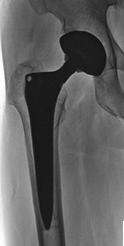

Capita che ci si accorga di un problema all’anca proprio in occasione di una valutazione di un paziente che si reca in cura per i dolori al ginocchio.In base alla gravità, all’età del soggetto, alla limitazione articolare presenta lo specialista può consigliare o meno l’intervento chirurgico.Durante l’intervento di artroprotesi vengono sostituite le parti anatomiche artrosiche con una testa del femore in metallo che articola con una cavità articolare in plastica che garantisce la remissione dei sintomi. Nonostante il quasi immediato miglioramento articolare può, soprattutto in pazienti con dolori da anni, permanere uno stato di difficile gestione muscolare, essendo tutto il comparto alterato da molti anni.